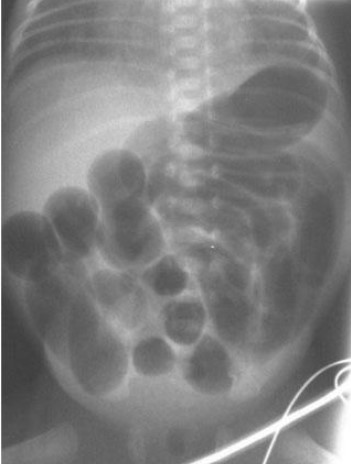

Common abdominal X-ray findings: